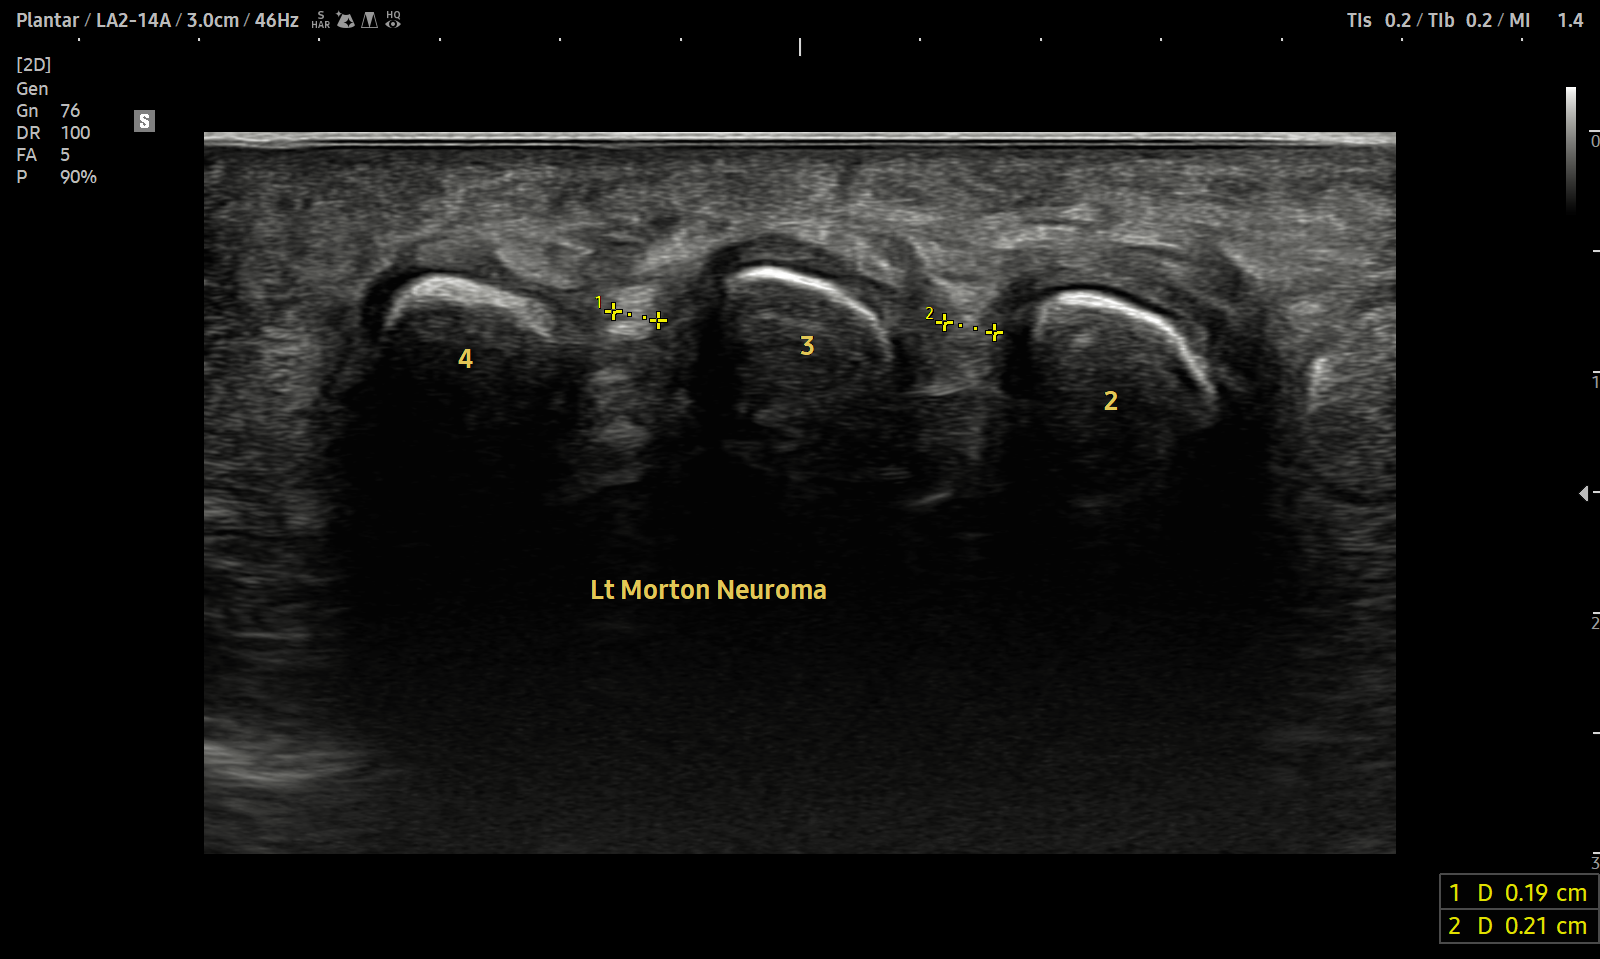

치료 후기에 사용된 전/후 검사 사진은 동일 인물의 결과이며 각 지점 동일 조건에서 촬영되었습니다.

개인에 따라 치료 결과에 차이가 있을 수 있으며, 부작용이 발생할 수 있습니다. 내원 후 충분한 상담을 받으시고 치료를 진행하시면 됩니다.

- 치료기간 : 2024 . 4 . 26 ~ 2025 . 6 . 17

- 치료횟수 : 30회